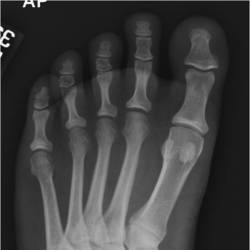

Gallery of Unlabled Radiographs from Lecture (Dr. French) - 2020

Click a thumbnail to enter the gallery display. Click the file name link at the bottom left of the gallery display to view the image at high resolution.